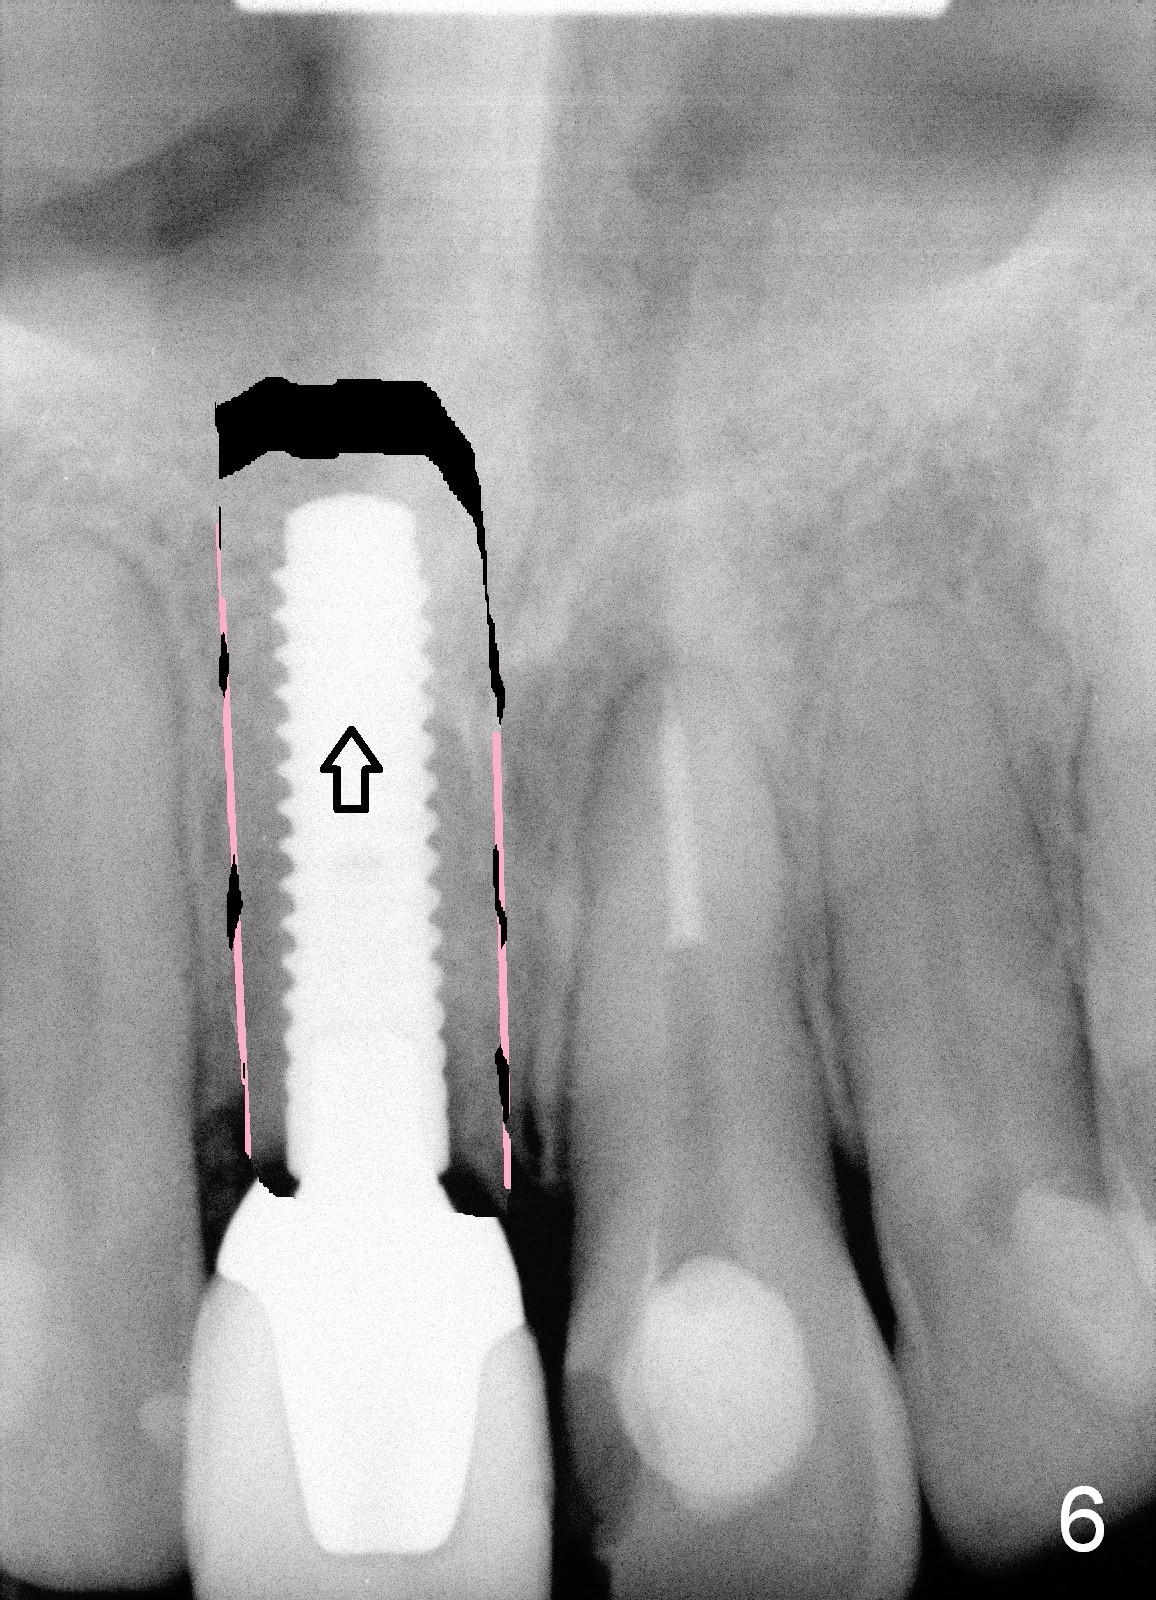

In contrast, delayed implant is most likely associated with mal-positioning in 3 D, including invasion of the nasal floor (Fig.3) due to bone loss. When segemental osteotomy is needed, the transverse cut is difficult (Fig.4). The implant bone segment may be not stable once moved (Fig.5), since no block graft can be inserted, not to mention trauma and hemorrhage in the nasal floor. The segment may relapse (Fig.6).